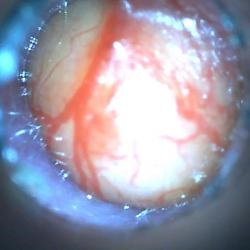

Prima etapă de inspecție a unui animal bolnav este otoscopia.

Pentru a selecta tactica corectă de tratament, luarea unei frotiuri din canalele auditive pentru cercetare citologică și cultură bacteriologică sunt activități foarte importante.

Otita urechii medii duce la abcese posterioare.

85 și șobolanii au fost diagnosticați cu otita microbiană pe baza otoscopiei, examinarea citologică din NSP și o imagine clinică.